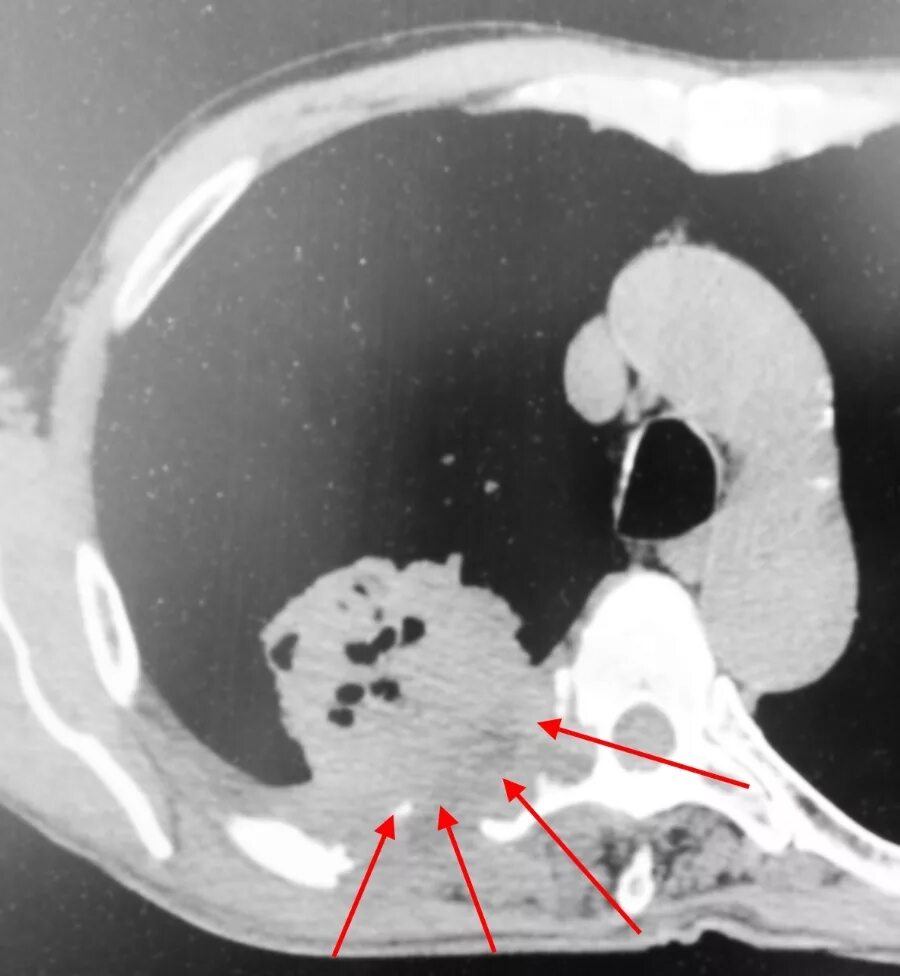

Как на кт выглядит рак